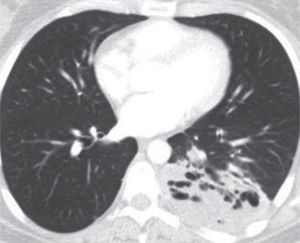

El pulmón en la fibrosis quísticaLa importante morbimortalidad de la FQ está relacionada fundamentalmente con la afectación pulmonar y sus complicaciones, condicionando el pronóstico. La alteración de la proteína CFTR provoca cambios en la reología del moco y en el aclaramiento mucociliar y una reacción inflamatoria exagerada que se localiza fundamentalmente en la vía aérea. Las secreciones obstruyen las vías aéreas y alteran la eliminación de microorganismos potencialmente patógenos, favoreciendo la infección crónica. Esta infección-inflamación se asocia con un daño progresivo con inflamación neutrofílica, desarrollo de bronquiectasias, neumopatía crónica progresiva con destrucción del parénquima pulmonar, deterioro de la función pulmonar e insuficiencia respiratoria7.

Las pruebas de imagen (TC, RM), la exploración funcional pulmonar y los estudios microbiológicos son las herramientas básicas para el diagnóstico y seguimiento de la afectación respiratoria en la FQ8–10. La TC de tórax es la prueba clave para conseguir el diagnóstico precoz de la afectación pulmonar en la FQ, y también es útil, y con más precisión que las pruebas funcionales, para estimar la gravedad y la progresión de la afectación pulmonar, ayudando a valorar la respuesta al tratamiento y a tomar decisiones sobre nuevos tratamientos, ajustándolos a la gravedad de las lesiones. Una progresión rápida del atrapamiento aéreo y de las bronquiectasias en la TC se ha asociado con la presencia de infección pulmonar y con peor pronóstico. La exploración de la función respiratoria muestra la existencia de un patrón obstructivo que va progresando en el tiempo, y que asocia la existencia de atrapamiento aéreo e hiperinsuflación pulmonar.